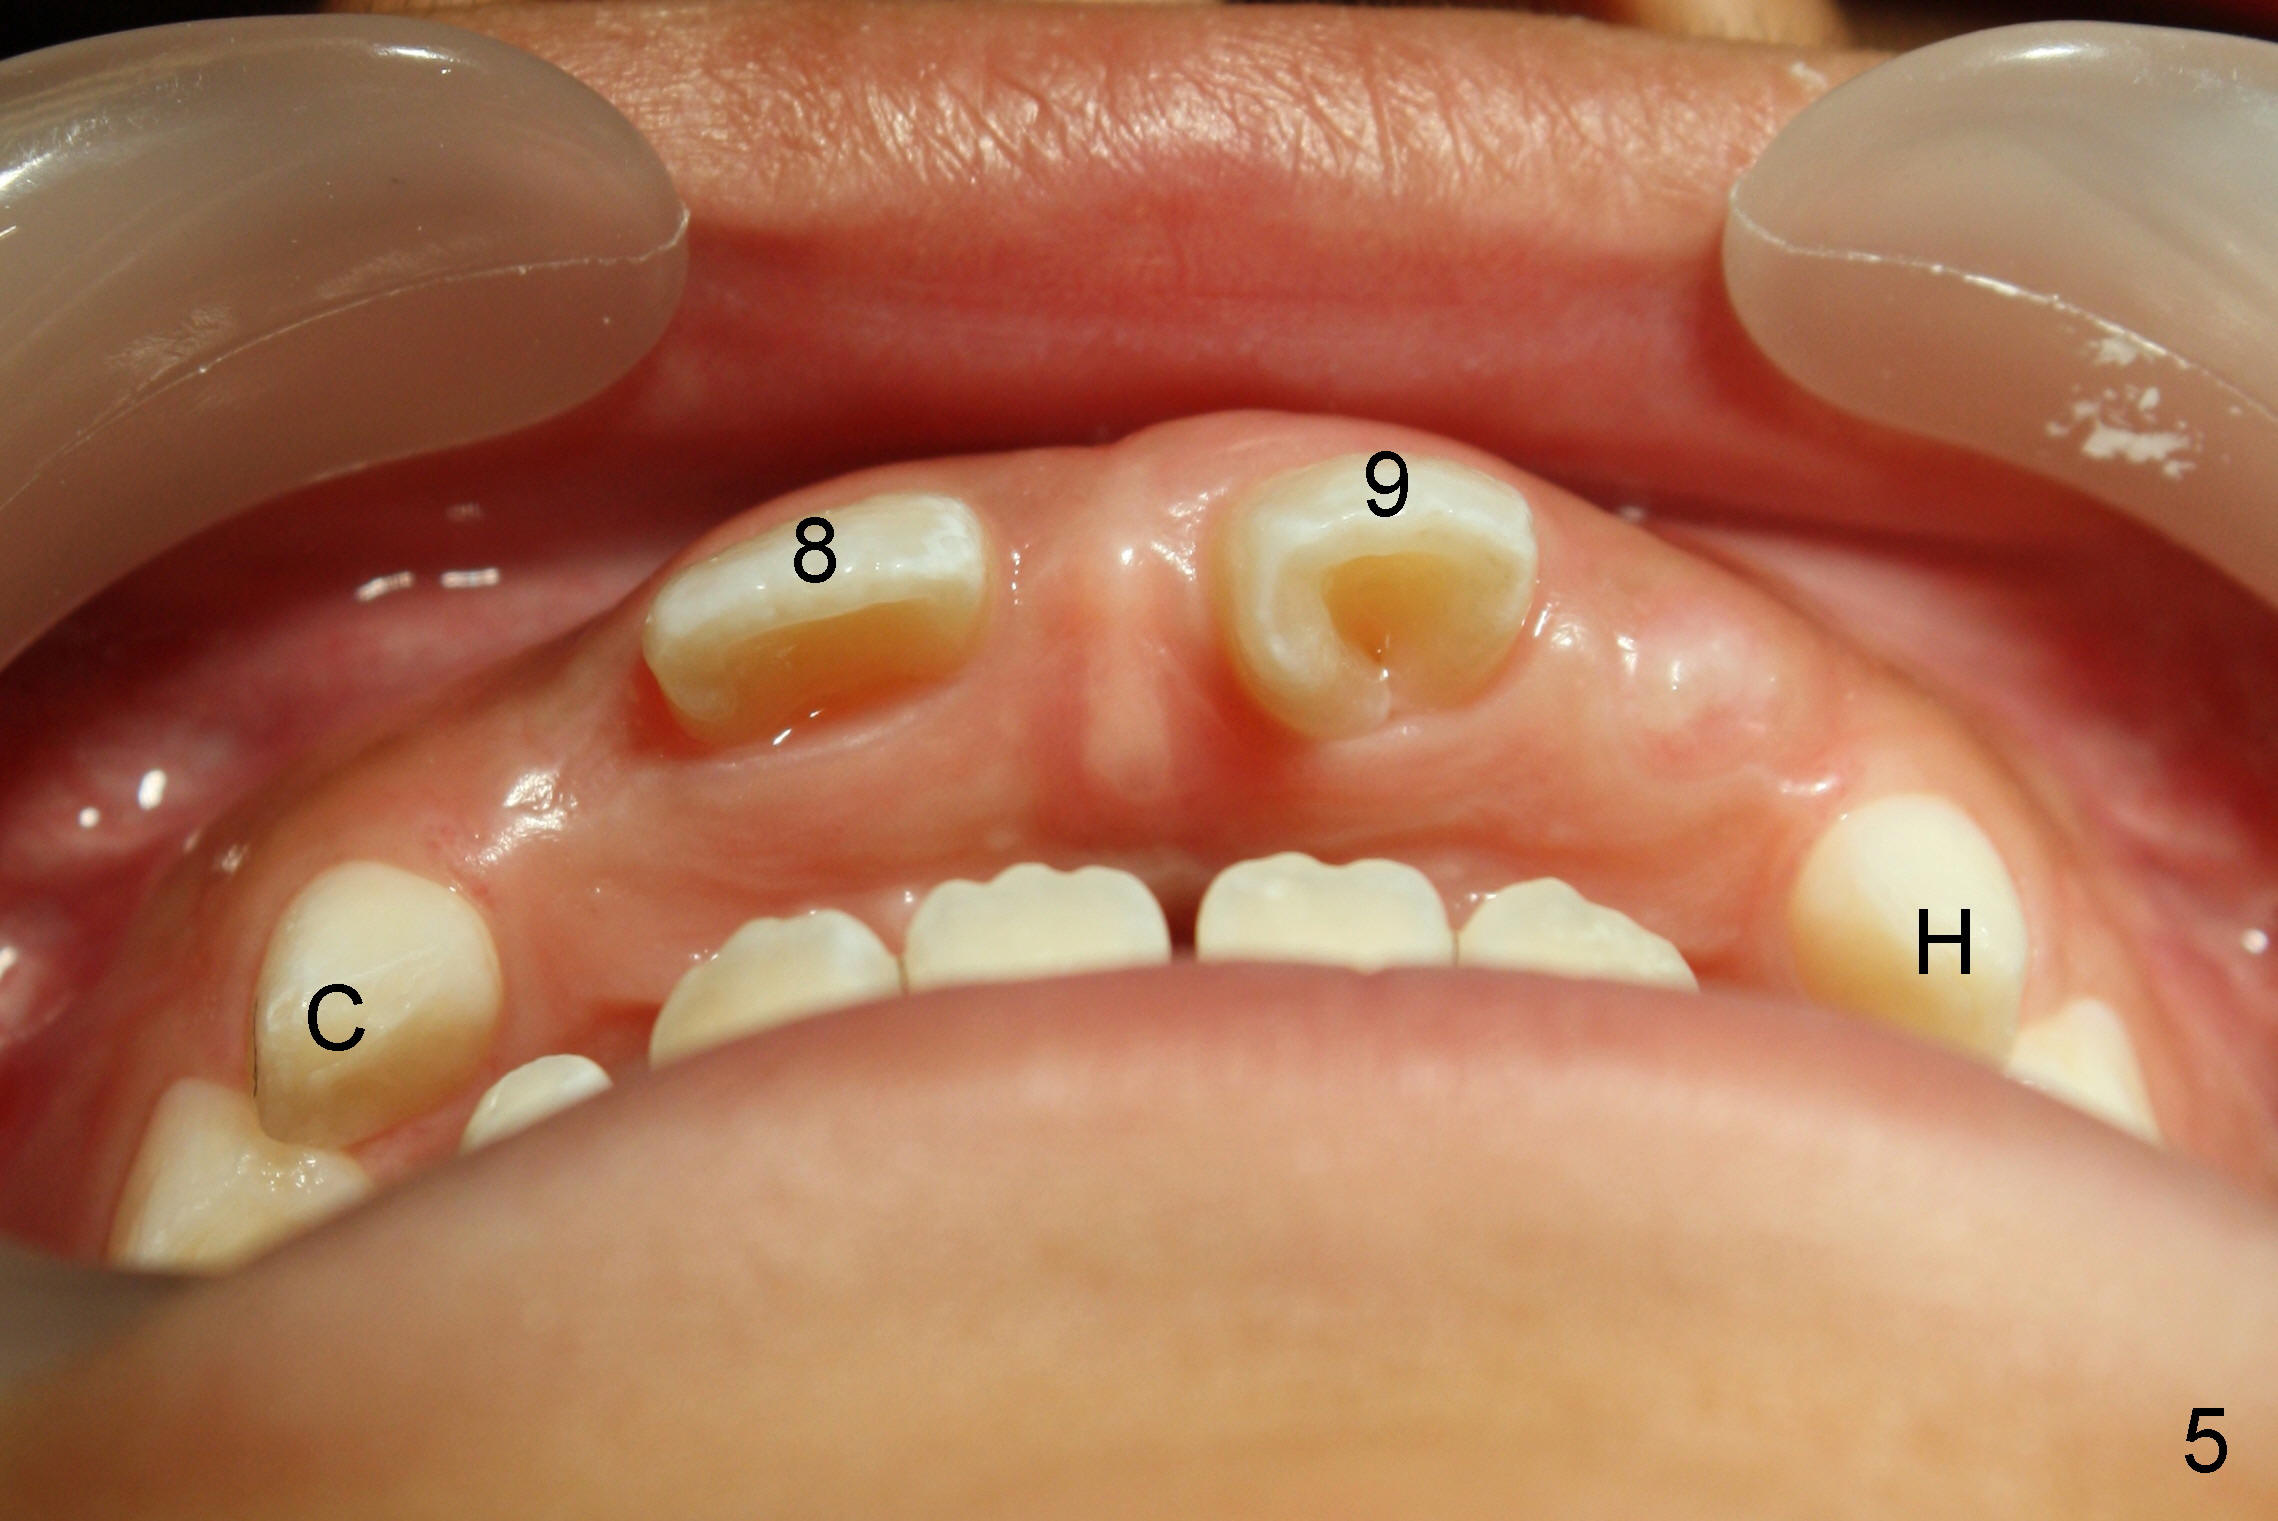

A seven-year-old co-operative boy presented to my office for composite. Exam shows open bite and a large diastema between the erupting upper central incisors (Fig.1-4). His mother notices that the diastema is more due to lateral displacement of the right central than the left central's (compare to Fig.1: black dashed line). She asks whether the uneven displacement will interfere with eruption of the upper right lateral incisor (Fig.2,3, as compared to Fig.4). She is interested in early ortho.

There are three questions. Will the right lateral erupt by itself and the diastema self corrects? When can we start ortho? How can we treat deep cingulum of #9 (Fig.2 >), removing marginal ridges or placing composite in the cingulum? The purpose of cingulum treatment is to prevent caries. Do we also need to add composite to #9 proximal surfaces to make it look as wide as #8? Thanks.

At the age of 7 years and a half, the tooth #10 is going to erupt (Fig.5). The space for #7 is narrower than that of #10. The mom chooses to watch for another six months